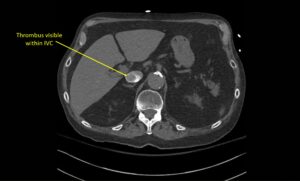

Wolff A, et al. Right atrial thrombosis. CT axial, IVC 1

Wolff A et al. Right atrial thrombosis. CT axial IVC 1